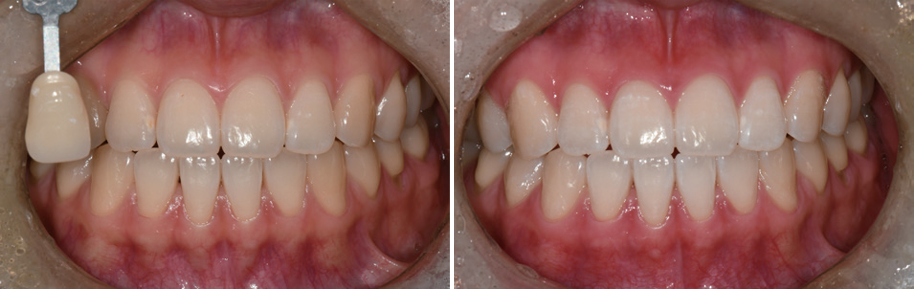

나이가 들면서 음식물 섭취로 서서히 치아가 어두워진 경우에는 치아 표면에 미백제를 발라서 색소를 제거하는 방식인 생활치 미백을 할 수 있습니다. 카바마이드 퍼옥사이드 등 미백제가 치아 표면의 색소들과 반응하는 원리입니다. 진료실에서 광선을 쬐면서 1~2시간 미백제를 발라서 치아를 밝게 만들거나, 치아의 본을 떠서 특수한 틀을 만들어서 집에서 미백제를 넣고 장치를 끼우는 방법을 사용하게 됩니다. 상황이나 생활습관 등에 따라서 주치의가 적절한 미백 방식과 시기, 횟수 등을 정하게 됩니다. 만약 치아를 다쳐서 안쪽의 신경이 죽어서 어두워진 경우라면 치아 안쪽의 근관(신경)치료를 먼저하고 치아 내부에 미백제를 넣어서 밝게 하는 실활치 미백치료를 합니다.

미백 전후